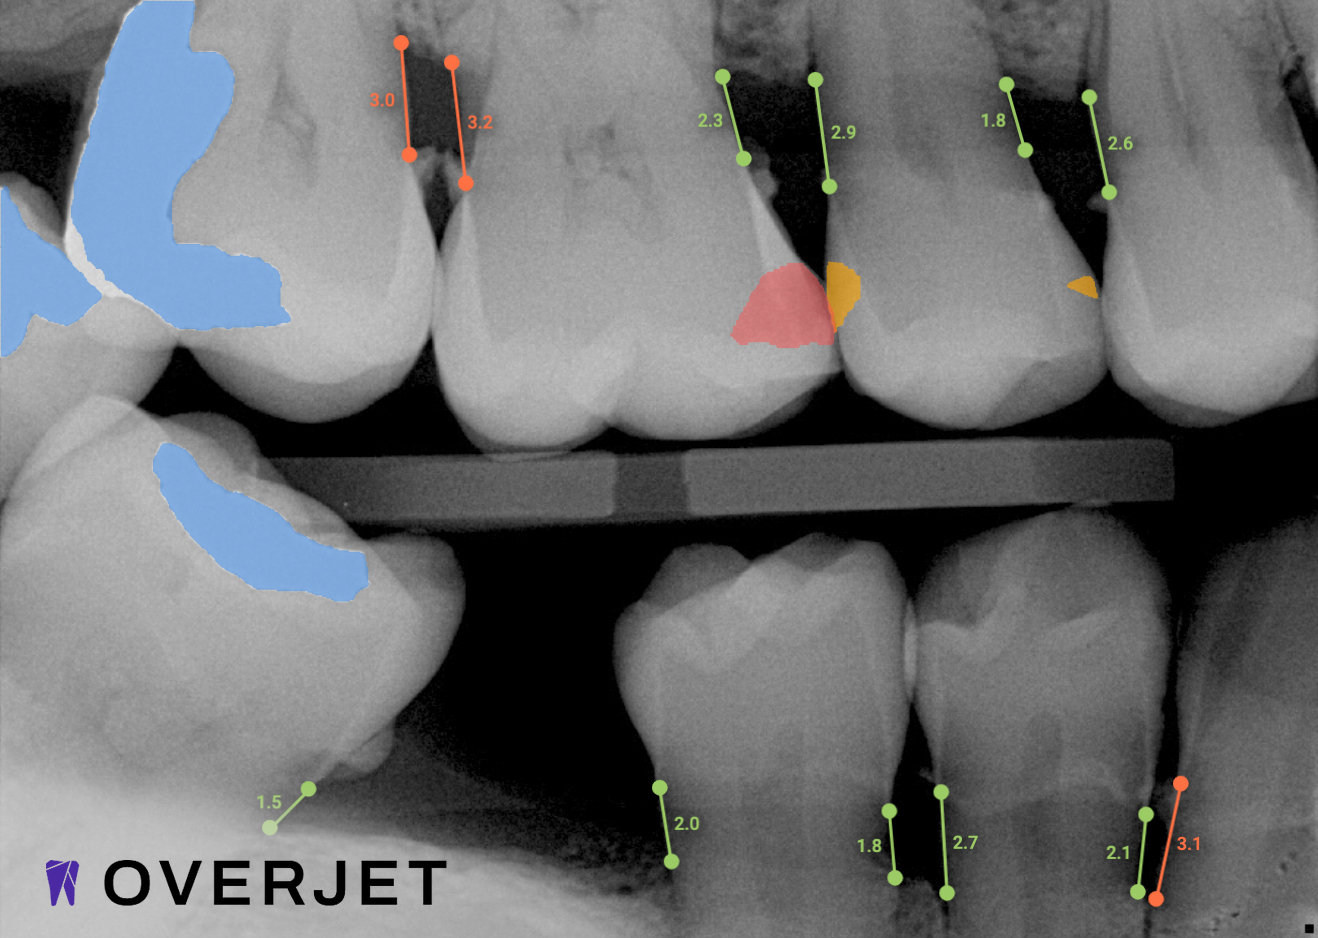

Overjet AI's  patient-centric technology combines human intelligence with the power of artificial intelligence.

Best in class dental care for every patient, on every visit.

Confidence in Your Diagnosis

Our practice is proud to provide the best technology in the dental industry, including Overjet AI for instant X-ray analysis.

Overjet’s artificial intelligence technology transforms traditional black-and-white X-rays by adding a layer of data that instantly outlines decay (cavities) and measures bone loss. This makes it easy for you to see your results alongside your dentist.  It’s like getting a second opinion delivered instantly. With Overjet’s analysis and easy-to-read presentation, you will have the information you need to make an informed decision about your oral health. Together, we’ll review your findings and discuss the best steps to take to achieve your goals.